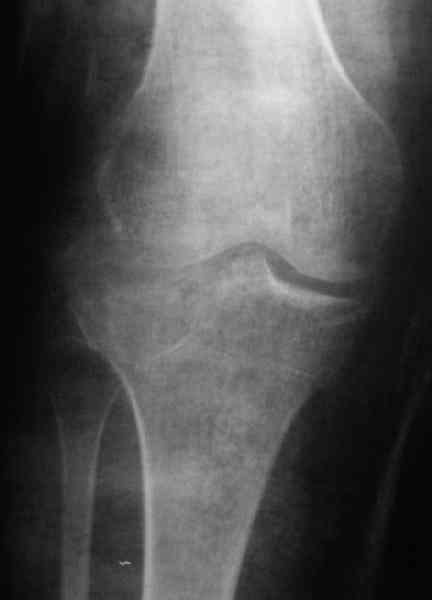

Уважаемый Абдурашид. Если нет противопоказаний , то из оперативных способов, я бы рекомендовал следующие: Полное замещение наружного мыщелка аллотрансплантатом либо открытая репозиция с элевацией и замещение дефекта ауто или аллокостью. В Ваших условиях , я бы рекомендовал второй способ. Во-время элевации необходимо разъединить фрагменты со стороны сустава ( надсечь скальпелем по линиям перелома, а затем тонким остеотомом их разъединить. При помощи долота произвести неполную остеотомию ( захватите не менее 1,5 - 2 см губчатой кости и поднять фрагменты, визуально отрепонировать и фиксировать 2-3 спицами. Дефект заместить костным ауто или аллатрансплантатом. Окончательная стабилизация пластиной ( лучше с угловой стабильностью, либо АВФ - позволит спокойно устранить угловую деформацию.

Недавно поступила больная через 1,5- 2 месяца.